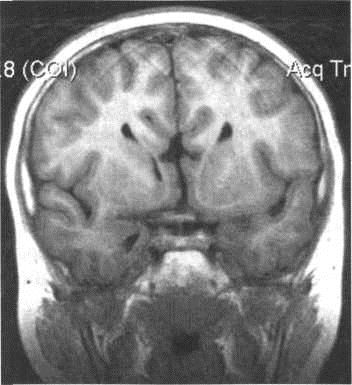

Мал. 3.10. Кіста прозорої перегодки. МРТ.

а - Т2-ВІ, аксіальна площина. Кіста розташовується між передніми рогами бічних шлуночків, спереду обмежена коліном мозолистого тіла. б - в режимі Т1, корональна площину. Кіста має овальну форму, контури її опуклі, надає об'ємне вплив на передні роги бокових шлуночків.